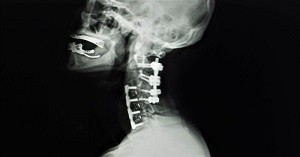

PCF is a surgical procedure that fuses two or more cervical spine bones together along the sides of the bone using a posterior incision. Bone graft or bone graft substitute is placed along the sides of the spine bones, which over time, fuses together. PCF may be performed with or without a posterior decompression (Posterior Cervical Laminectomy in Newport Beach) and/or instrumentation (use of metal screws or rods), which contributes to stability, especially with multi-level fusions and increases the success rate of fusion.

Patients will return for a follow-up visit to see Dr. Louis about 12-14 days after the PCF procedure. Medications will be refilled if necessary. During the follow-up visit, Dr. Louis will check the incision and the stitches or staples will be removed and an X-ray will be taken to check if the fusion area is stable and if it’s healing properly. Patients will be asked to return for more follow-up visits about 4-6 weeks after the initial follow-up visit. Around 8-12 weeks after surgery, the patient will be given a prescription to begin physical therapy to help improve the range of motion.